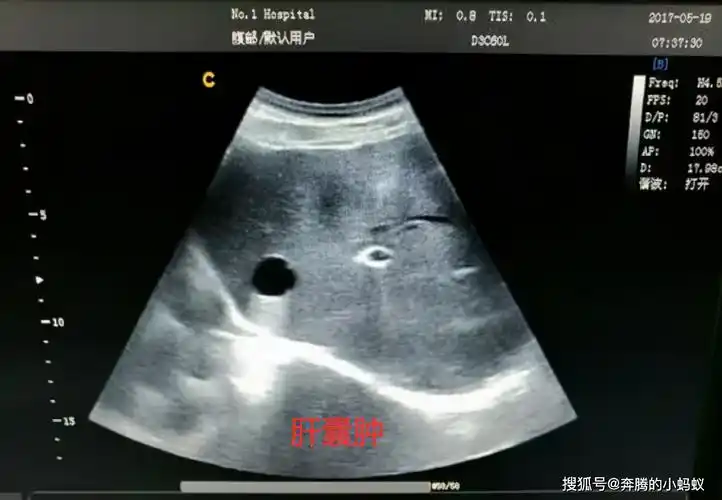

肝囊肿_新浪财经_新浪网

肝脏b超

正常肝脏b超图